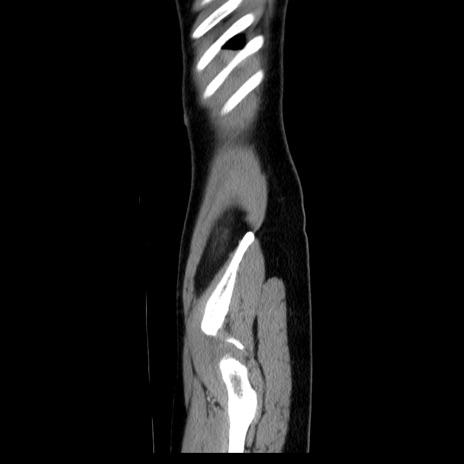

MRI(4日後)